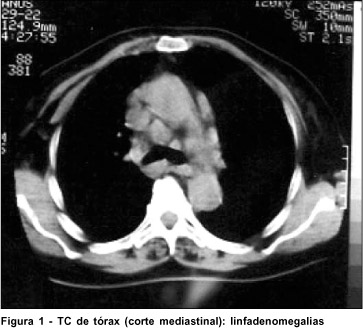

Há 10 anos apresentou nódulos cutâneos, adenopatia paratraqueal, obstrução nasal crônica e fadiga. Foi realizada investigação clínica e feito o diagnóstico de sarcoidose, corroborado pelos exames complementares: 1) TC de tórax que mostrou pulmões com acentuação das marcas intersticiais especialmente nas bases, brônquios com paredes espessadas, porém não dilatadas; presença de imagens mediastinais e hilares compatíveis com linfadenomegalias (Figura 1); 2) Cintilografia pulmonar com gálio 67: mostrou distribuição do isótopo de forma aumentada em grau moderado principalmente em base e região mediana de tórax, com áreas focais mais intensas em base pulmonar esquerda e direita posteriormente; 3) Dosagens sanguíneas de cálcio e ECA (enzima conversora da angiotensina I) mostraram-se aumentadas. O diagnóstico foi confirmado mediante biópsia de gânglios paratraqueais: o exame histopatológico mostrou gânglio linfático com sua estrutura parcialmente alterada pela presença de numerosos granulomas constituídos por macrófagos, tendo de permeio raras células gigantes de tipo Langerhans; na periferia observa-se moderada quantidade de linfócitos sem atipias. Pesquisas de bacilo álcool-ácido resistente e fungos resultaram negativas.